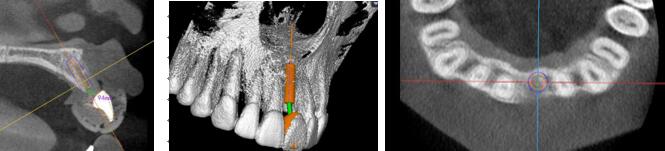

術(shù)前種植體規(guī)劃

術(shù)中實(shí)時(shí)導(dǎo)航

1.4mm球鉆定位△

2.3mm球鉆△

導(dǎo)航指示下2.2先鋒鉆擴(kuò)孔,導(dǎo)向桿檢查軸向及定位△

2.8mm擴(kuò)孔鉆△

26距25為3mm,26距27為4.71mm 26牙為4.10x11.50mm植體